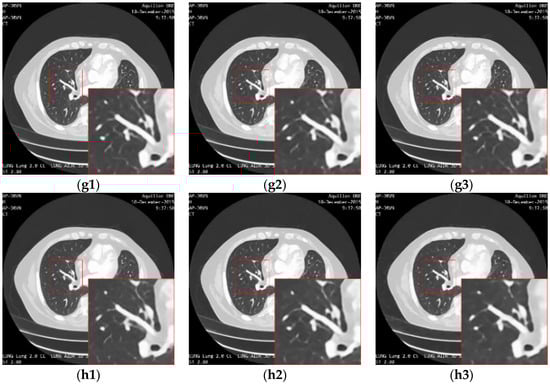

Figure 14 shows the result of enhancing the quality of images corrupted by noise and low-resolution through different methods. The bicubic interpolation method provides the worst performance, with much remaining noise and artifacts along the edges in the high-resolution image. This is mainly because the bicubic method simply makes use of the intensities in the neighborhood without taking the structure information into account. When the noise is distributed around the image, the noise intensities are also calculated by the interpolation function in the high-resolution image, resulting in the artifacts and blurring as shown in Figure 14(c1–c3). The deep learning methods perform better than the classic interpolation method because they make use of the visual features of the image so that the noise can be eliminated. However, the SRMD needs to know the noise level as prior knowledge. When the actual noise is different from the assumed noise, the performance is not as convincing. In our experiment, the noise level is unknown and was set by the user blindly, so it can be considered in Figure 14(d1–d3) that the structures, edges, or other details are not reconstructed in the resulted image. As shown in Figure 14(e1–e3), the SRCGAN can recover the structures in the medical image well, but some noise cannot be eliminated well because the GAN may consider this noise as tiny structures by mistake. In contrast, as shown in Figure 14(f1–f3), the RED-CNN can provide a good performance in the removal of noise because the U-net structure can filter out the noise features very well. However, it will over-smooth small edges in the image because it lacks the ability to preserve detailed information and perceptual features. As shown in Figure 14(g1–g3), the RDN method performs better than the previous methods because the residual-dense block can extract and reuse the image features better than the simple convolution layer used in the SRMD, SRCGAN, and RED-CNN. However, noise remains in the high-resolution image due to the ability of the skip connection to transfer noise features to the last fully connection layer as well as the structure features. Moreover, the RDN also needs to have prior knowledge of the noise level in the image, which makes it unable to adapt to a blind case. Our proposed method takes advantage of the RDN method and improves it by embedding an inception block into the skip connection routines. Moreover, it makes use of the noise estimation network to automatically calculate the noise level and takes that as the input of the quality enhancement network. Therefore, as shown in Figure 14(h1–h3), the proposed framework provides superior performance on noise removal and detail preservation during the super-resolution.

Figure 14.

The result of enhancement of the quality of images corrupted by noise with different levels and low-resolution through different methods. (a1), (a2) and (a3) are the input images with noise level 5, 10 and 15. (b1), (b2) and (b3) are the ground truth image. (c1), (c2) and (c3) are the images (a1), (a2) and (a3) processed by the bicubic method. (d1), (d2) and (d3) are the images (a1), (a2) and (a3) processed by the SRMD method. (e1), (e2) and (e3) are the images (a1), (a2) and (a3) processed by the SRCGAN method. (f1), (f2) and (f3) are the images (a1), (a2) and (a3) processed by the RED-CNN method. (g1), (g2) and (g3) are the images (a1), (a2) and (a3) processed by the RDN method. (h1), (h2) and (h3) are the images (a1), (a2) and (a3) processed by the proposed method.

Figure 15 shows the absolute differences between the images restored by different methods and the ground truth image. It demonstrates that the proposed method can eliminate noise the most while removing the anatomical structures to the least extent.

Figure 15.

Absolute differences between the images (noise level = 20) restored by different methods and the ground truth image. (a) is the bicubic interpolation, (b) is the SRMD, (c) is the SRCGAN, (d) is the RED-CNN, (e) is the RDN, and (f) is the proposed method.